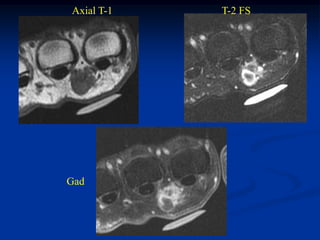

Case #1197 CLASSIC 37 yearfemale with hibernoma triceps m Sagittal T-1 MRI

Case #1197.1 Sag T-1 MRI Cor T-1 MRI Axial T-1 MRI 38 year female with painless hibernoma anterior thigh

Sagittal T-2 MRI Sagittal Gad MRI